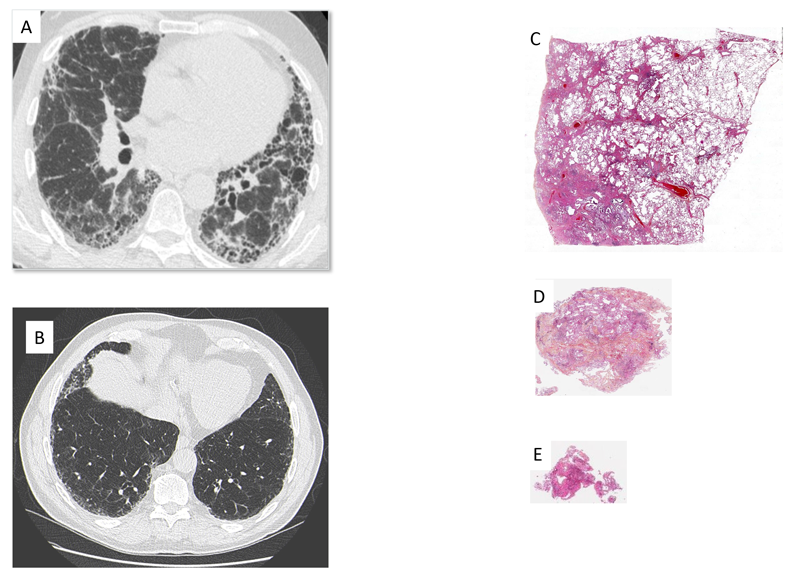

L’identification de l’aspect de PIC peut être réalisée sur l’imagerie ou sur l’histologie (biopsie pulmonaire). Les progrès du scanner et les confrontations entre les données d’imagerie et anatomopathologiques ont permis de mieux caractériser l’atteinte interstitielle vue au scanner et de limiter le recours à une biopsie pulmonaire. Il a d’abord été démontré qu’un aspect de PIC au scanner, défini par la présence d’images en rayon de miel et une topographie sous-pleurale et basale des lésions, avait une valeur prédictive positive de plus de 95 % de PIC histologique, permettant ainsi de se passer d’une confirmation histologique. Il a ensuite été montré qu’un aspect de «PIC probable» au scanner, défini par la présence de bronchectasies par traction périphériques et de réticulations, de topographie prédominante sous-pleurale et basale, sans rayon de miel, permettait également, dans un contexte clinique évocateur de FPI, de prédire une PIC histologique et ainsi de poser un diagnostic de FPI sans recours à une confirmation histologique [2].

Malgré ces progrès radiologiques permettant de diminuer le recours à une biopsie chirurgicale et en l’attente de confirmation des résultats prometteurs des analyses automatisées des scanners thoraciques, il est encore parfois nécessaire d’obtenir une confirmation histologique de PIC.

Les progrès chirurgicaux et la meilleure sélection des patients ont permis de diminuer la morbi-mortalité de cet examen invasif. Parallèlement la technique de cryobiopsie a été développée. Il s’agit d’une technique endoscopique dans laquelle une cryosonde est introduite par le canal opérateur. Cette sonde permet de congeler les tissus avoisinants sur plusieurs millimètres en quelques secondes. Un morceau de poumon gelé de 5 mm d’arête au moins peut ainsi être obtenu et permet une analyse histologique représentative de parenchyme pulmonaire. Ainsi dans une étude prospective récente, dans 95 % des cas, si le degré de confiance dans le diagnostic était élevé, le diagnostic histologique proposé par cryobiopsie était concordant avec celui de la biopsie pulmonaire chirurgicale. En revanche, quand le degré de confiance était plus faible, la classification était modifiée pour 23 % des patients entre les 2 techniques[3]. De plus, d’autres techniques encore moins invasives sont en cours de développement, et une méthode basée sur l’analyse transcriptomique des biopsies transbronchiques pour le diagnostic de FPI est ainsi déjà approuvée aux États-Unis, bien que les données soient pour l’instant encore limitées[4].

Figure 3 Scanner représentatif de (A) Pneumopathie interstitielle commune, (B) Pneumopathie interstitielle commune probable. Prélèvement histologique représentatif prélevé (A) par biopsie pulmonaire chirurgical, (B) par cryobiopsie, (C) par biopsie transbronchique.